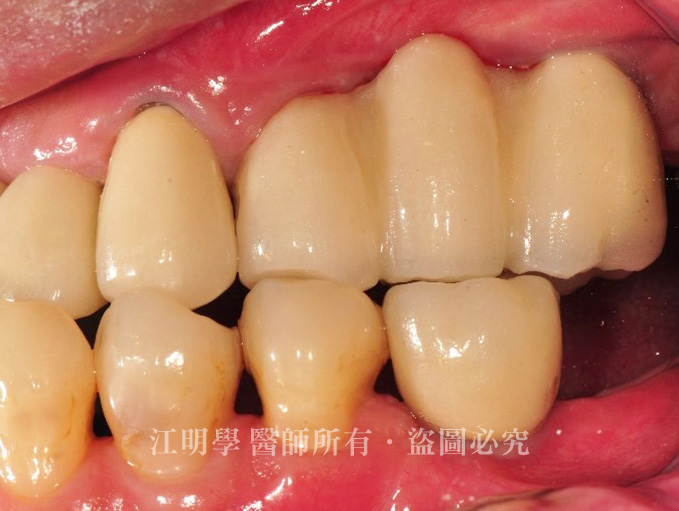

拆除既有固定式假牙,並考量牙齒長久使用性,為江先生進行根管治療與假牙膺復,以完整恢復牙齒的健康與功能。

接著利用人工植牙將缺牙部分重建起來,並重新設計牙齦高度,將咬合調整到最自然美觀的位置。

治療後:配合自然牙的狀態重建植牙,讓整體更加和諧。